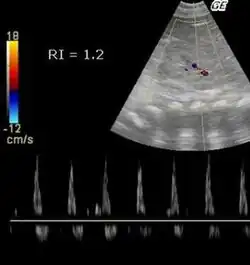

| >1 | Обратный ток крови во время диастолы |

После трансплантации почки у пациентов с RI> 0,8 наблюдается повышенная смертность.